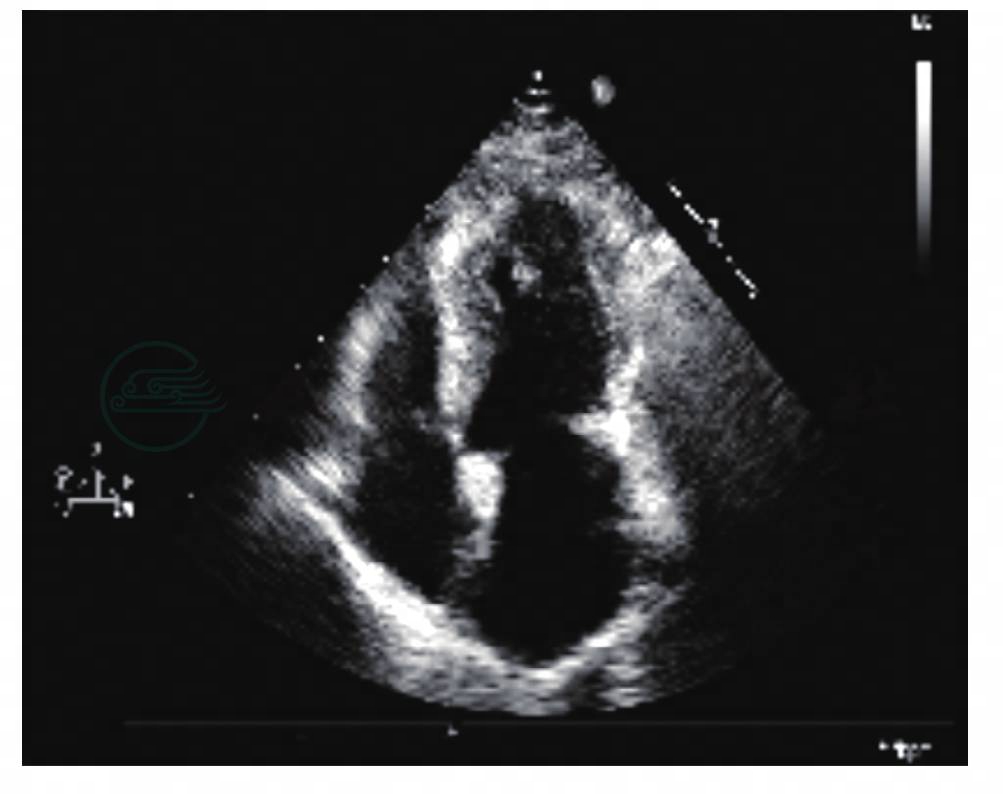

最近一次超声心动图(图16)显示左房轻度增大,余房室内径正常,室间隔基底段厚约22mm(与此前两次复查结果比较略有增厚),左室流出道内径较术前明显增宽,主动脉瓣缘散在钙化,累及瓣环,开放尚可,关闭欠佳,余瓣膜结构未见明显异常。心包腔未见异常。多普勒检查,左室流出道血流速度较术前明显减低,峰值流速2.0m/s,峰值压差约16mmHg。主动脉瓣少量反流,二尖瓣少中量反流信号。舒张期二尖瓣血流频谱E/A比值小于1。

图16 2013-10-11超声心动图